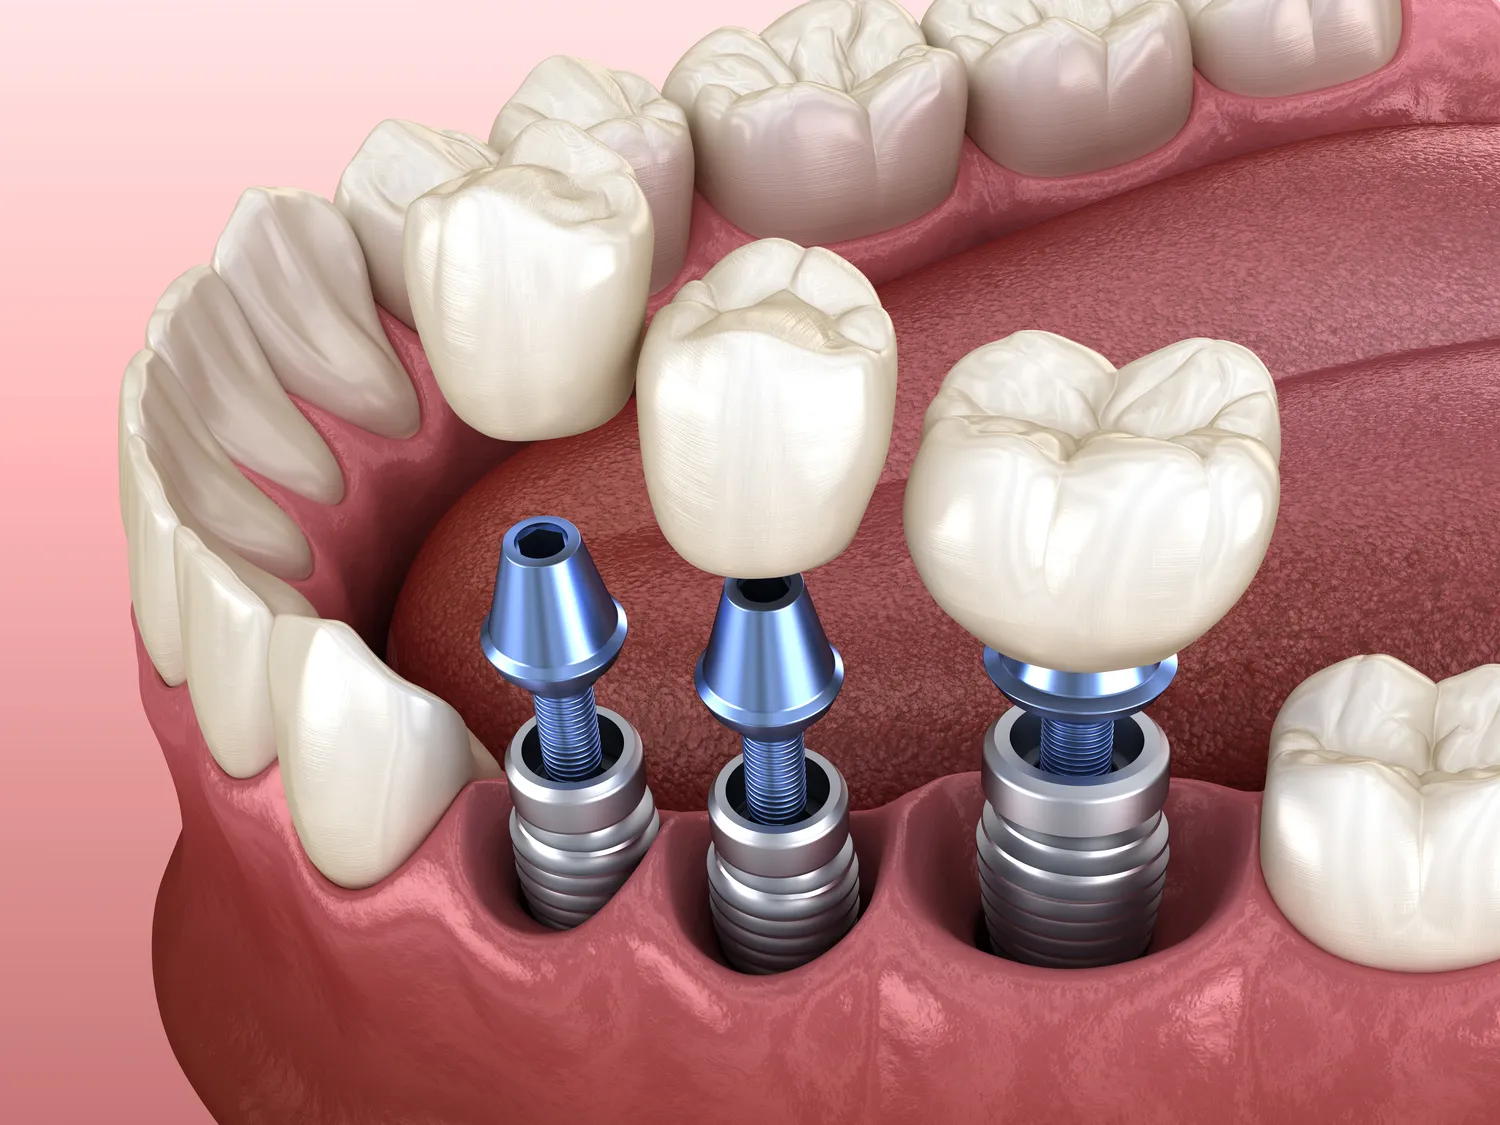

Implanty zębowe to nowoczesne rozwiązanie stosowane w stomatologii, które pozwala na zastąpienie brakujących zębów. W ich skład wchodzi tytanowy wszczep, który jest umieszczany w kości szczęki lub żuchwy. Proces ten polega na chirurgicznym wprowadzeniu implantu do kości, co pozwala na jego integrację z tkankami kostnymi. Dzięki tej metodzie pacjenci mogą cieszyć się stabilnością i funkcjonalnością, która przypomina naturalne zęby. Implanty zębowe są szczególnie polecane osobom, które straciły zęby na skutek urazów, chorób przyzębia czy innych problemów zdrowotnych. Po zakończeniu procesu gojenia, na wszczepionym implancie umieszczana jest korona protetyczna, która jest dostosowana do kształtu i koloru pozostałych zębów pacjenta. Dzięki temu implanty nie tylko przywracają funkcję żucia, ale także poprawiają estetykę uśmiechu. Warto zaznaczyć, że implanty zębowe są trwałym rozwiązaniem, które przy odpowiedniej pielęgnacji mogą służyć przez wiele lat, a nawet całe życie.

Proces zakupu i wszczepienia implantów zębowych składa się z kilku etapów, które wymagają staranności oraz współpracy ze specjalistą. Pierwszym krokiem jest konsultacja stomatologiczna, podczas której lekarz ocenia stan zdrowia pacjenta oraz wykonuje niezbędne badania diagnostyczne, takie jak zdjęcia rentgenowskie czy tomografia komputerowa. Na podstawie tych informacji lekarz podejmuje decyzję o możliwości wszczepienia implantu oraz planuje jego lokalizację. Kolejnym etapem jest przygotowanie do zabiegu, które może obejmować leczenie innych problemów stomatologicznych lub przygotowanie kości poprzez zabiegi regeneracyjne. Sam zabieg wszczepienia implantu trwa zazwyczaj od jednej do dwóch godzin i odbywa się w warunkach ambulatoryjnych. Po wszczepieniu implantu następuje okres gojenia trwający od kilku tygodni do kilku miesięcy, podczas którego implant integruje się z kością. Po zakończeniu tego etapu można przystąpić do wykonania korony protetycznej, która zostanie umieszczona na implancie.

Proces gojenia po wszczepieniu implantu zębowego jest kluczowym etapem, który ma istotny wpływ na sukces całej procedury. Czas gojenia może się różnić w zależności od indywidualnych predyspozycji pacjenta oraz specyfiki zabiegu. Zazwyczaj okres ten trwa od kilku tygodni do kilku miesięcy. W pierwszym etapie następuje proces osteointegracji, czyli integracji implantu z tkanką kostną szczęki lub żuchwy. To kluczowy moment, ponieważ stabilność implantu zależy od tego procesu. W przypadku pacjentów z dobrą jakością kości gojenie może przebiegać szybciej niż u osób z problemami kostnymi lub innymi schorzeniami zdrowotnymi. Po zakończeniu tego etapu można przystąpić do wykonania korony protetycznej. Ważne jest również to, aby pacjenci przestrzegali zaleceń lekarza dotyczących diety i aktywności fizycznej w okresie gojenia.